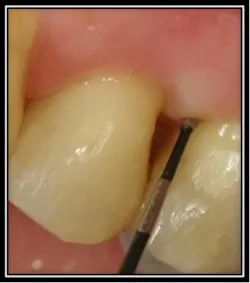

Photo 1

Photo 2 Photo #1 identifies the enamel projection. Photo #2 shows the curved unltrasonic insert removing the projection and cleaning into the furcation.